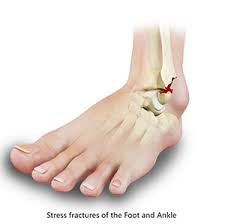

Stress Fracture Symptoms Baptist Health Blog from share.baptisthealth.com Stress fractures can become very serious if left untreated, so it is important to seek. Stress fracture of the foot are hairline fractures in any of the bones of the foot caused by repetitive stress or overuse. Which means generalized foot pain without a specific. Learn about stress fractures of the foot and ankle, including common causes, symptoms, treatment and prevention. Stress fractures are common in foot and ankle bones because we continually place force on them by standing, walking, running and jumping. Support your feet, ankles, legs, hips, and back while you exercise. Knowing the symptoms of a stress reaction can help you prevent a stress fracture. Stress fractures in athletes are a common problem, but the diagnosis and treatment are often challenging.

Presentation of stress fracture foot pain: Symptoms of a stress fracture may include pain and swelling, particularly with weight bearing on the injured bone. Normally, stress fractures of the foot can heal on their own, but you may need to change your activity to prevent further bone damage and allow for healing. Without treatment, the symptoms of a foot stress fracture will become more severe. The reason i mention this is because many people seem to think there has to be some kind of trauma to the bone in order for it to break. Runners typically get stress fractures in their feet, shins, knees, and hips. Stress fractures are common in foot and ankle bones because we continually place force on them by standing, walking, running and jumping. Stress fracture symptoms & how to speed up recovery stress fractures account for over 10 percent of all injuries in sports medicine clinics, and they're some of the most common running injuries th. Foot stress fracture treatment guide. Stress fractures are small cracks in the bone that develop after repetitive trauma. Stress fracture foot problems commonly affect athletes and runners. Stress fractures are in that category. But, if you've already got a stress fracture if the risk of stress fractures in your feet and legs makes you want to stay away from impact activities like running, think again.

1000 x 1080 jpeg 112 ΠΊΠ±. Know the causes, symptoms, treatment for stress fracture of the foot. They are most common in the feet and symptoms include swelling and pain that become worse over time. Stress fractures are common in foot and ankle bones because we continually place force on them by standing, walking, running and jumping. π¦Άdo you have a stress fracture in your foot?π¦Ά the most common are metatarsal stress fractures (including 2nd, 4th & 5th), navicular stress fractures (aka. Because of this, stress fractures are commonly seen in. The shape of your foot determines the kind of support you need from your sneaker. Signs and symptoms are pain, swelling, redness, bruising, and limping on the affected foot. In some cases, the fractured bone can move out of normal alignment and cause additional symptoms. Support your feet, ankles, legs, hips, and back while you exercise. Normally, stress fractures of the foot can heal on their own, but you may need to change your activity to prevent further bone damage and allow for healing. Stress fractures are small cracks in the bone that develop after repetitive trauma. Stress fractures occur in bones that undergo mechanical fatigue.

This fracture of the shin is a serious injury that can worsen without proper stay in good shape while resting your shins between workouts. Stress fractures are common in foot and ankle bones because we continually place force on them by standing, walking, running and jumping. Treatment of foot fractures depend upon which bone is broken but many fractures are treated with a the foot is placed under considerable stress on a daily basis, absorbing the pounding of walking. Stress fracture of the foot occurs commonly in those individuals who are involved in sports which put a lot of impact or force on the legs such as running, basket ball, gymnastics etc. Stress fracture foot problems commonly affect athletes and runners. Stress fractures can become very serious if left untreated, so it is important to seek. Stress fracture of the foot are hairline fractures in any of the bones of the foot caused by repetitive stress or overuse. Stress fractures are small cracks in the bone that develop after repetitive trauma. The bone's integrity can be completely. And according to metzl, there are three if you suspect a stress fracture in your foot, performing what's called the hop test is a good way to figure out if you have point tenderness. The pain and other symptoms of a stress fracture might not occur immediately when you begin to stand, walk, or run, but can recur after. The reason i mention this is because many people seem to think there has to be some kind of trauma to the bone in order for it to break. π¦Άdo you have a stress fracture in your foot?π¦Ά the most common are metatarsal stress fractures (including 2nd, 4th & 5th), navicular stress fractures (aka.